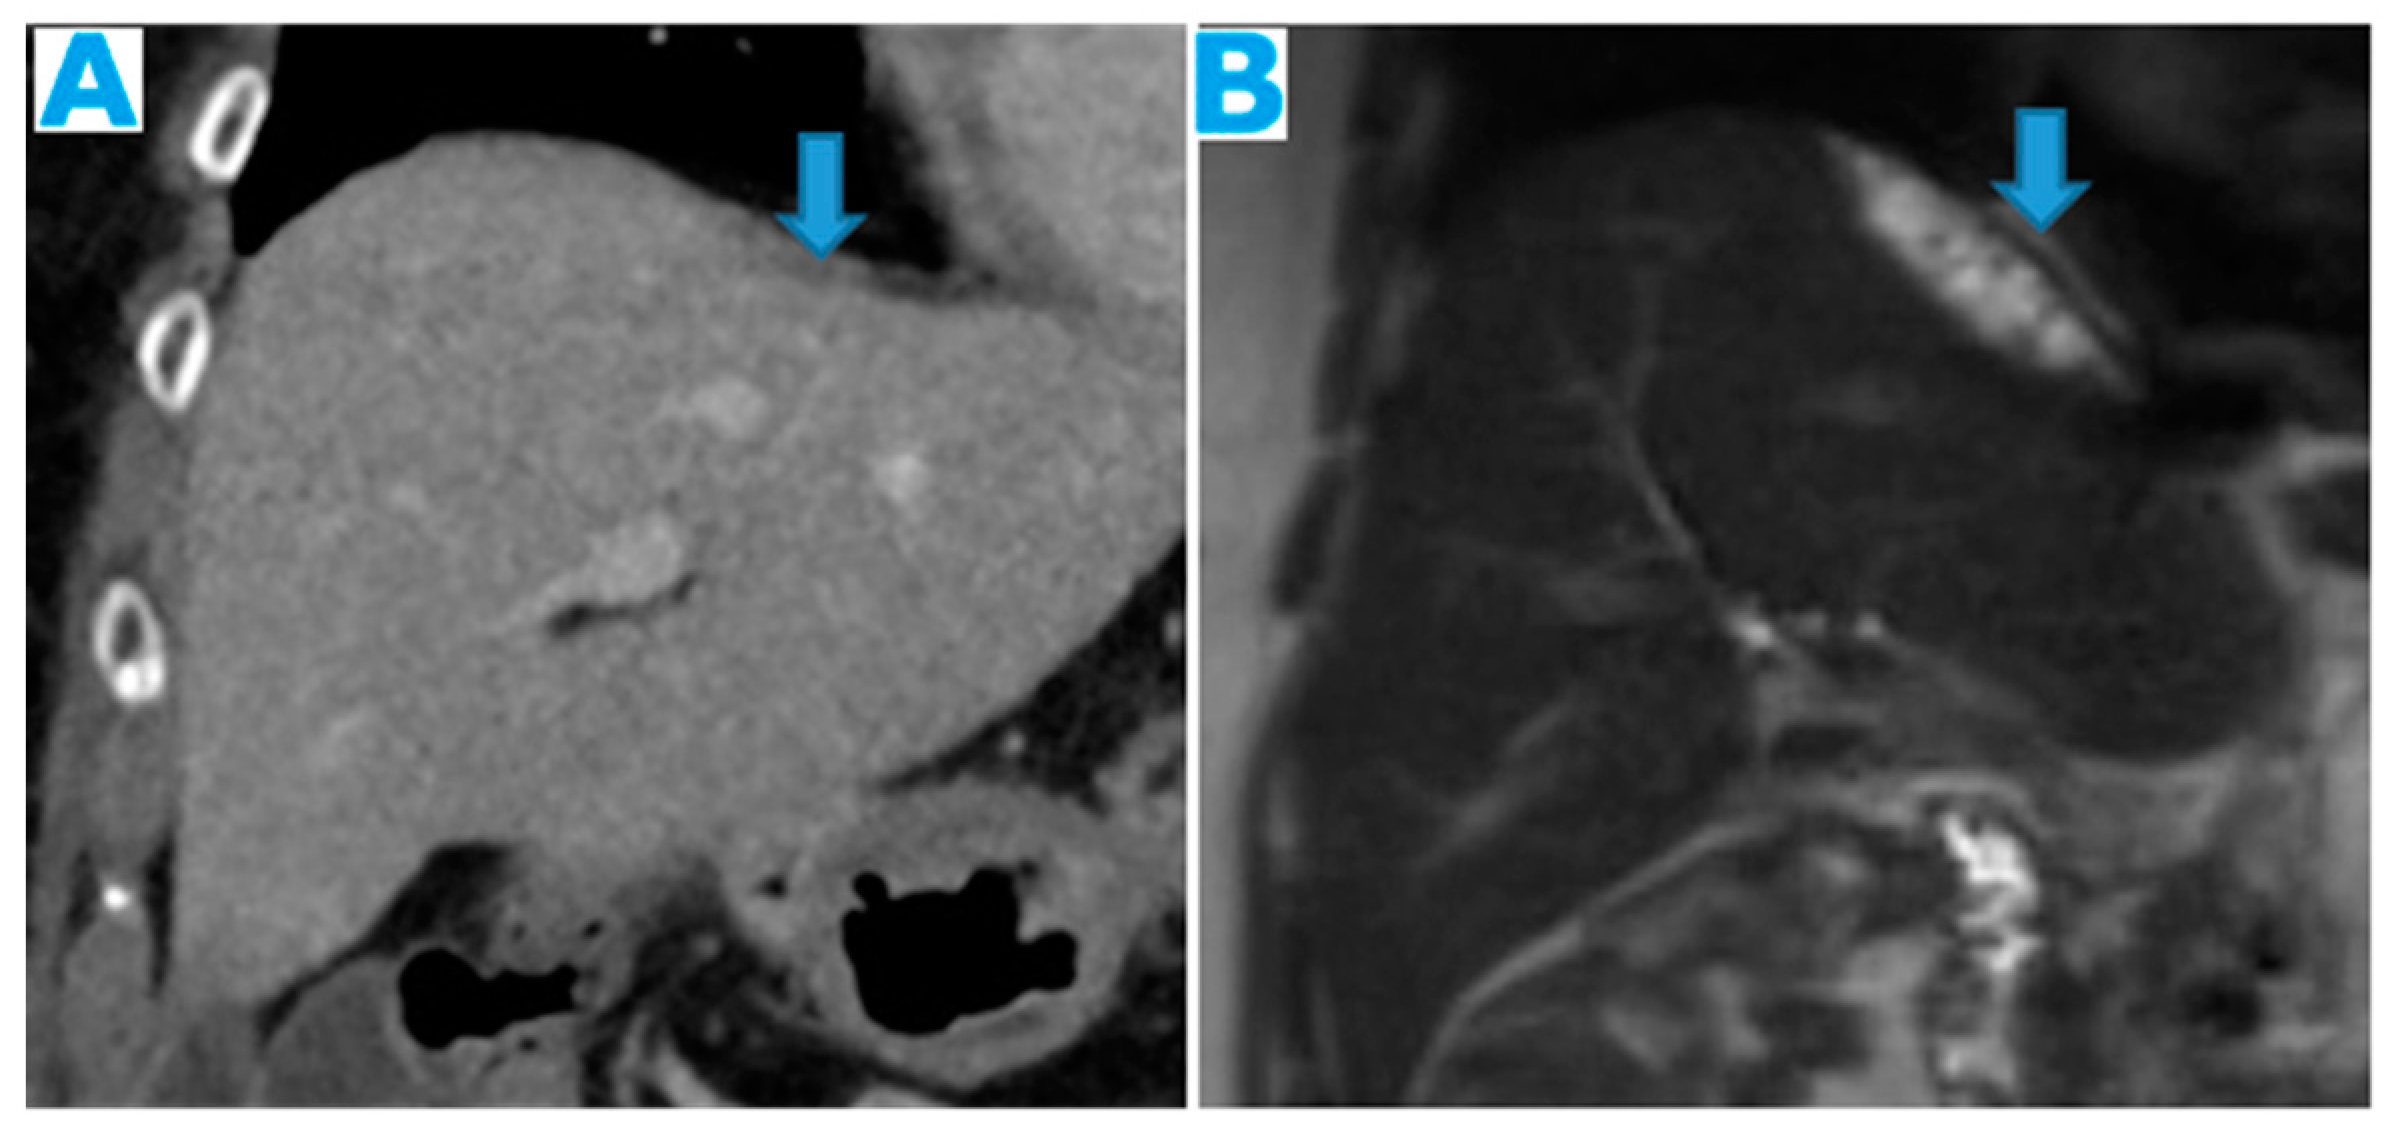

Figure 10.

Axial T2WI (A), axial NE FST1WI (B). PC from ovarian serous carcinoma: Subcapsular hepatic deposit, presenting a fatty plane around (arrow) that excludes secondary hepatic invasion.